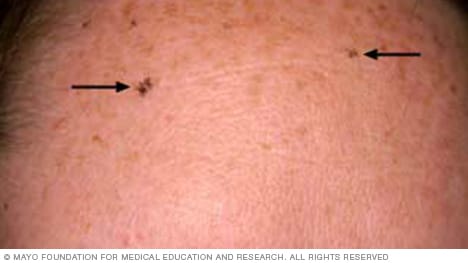

Solar lentigines on the forehead

Solar lentigines (len-TIJ-ih-neez) are flat spots that are darker than the skin around them. They are usually tan, brown or dark brown, depending on skin color. Typically, they are darker than freckles. Solar lentigines usually have oval to round shapes with uneven edges. They can be different sizes. They tend to show up on areas most exposed to the sun, such as the head, face, hands, arms and upper body. Also called liver spots, they are common in older adults. But children with white skin who spend a lot of time in the sun also may develop solar lentigines.